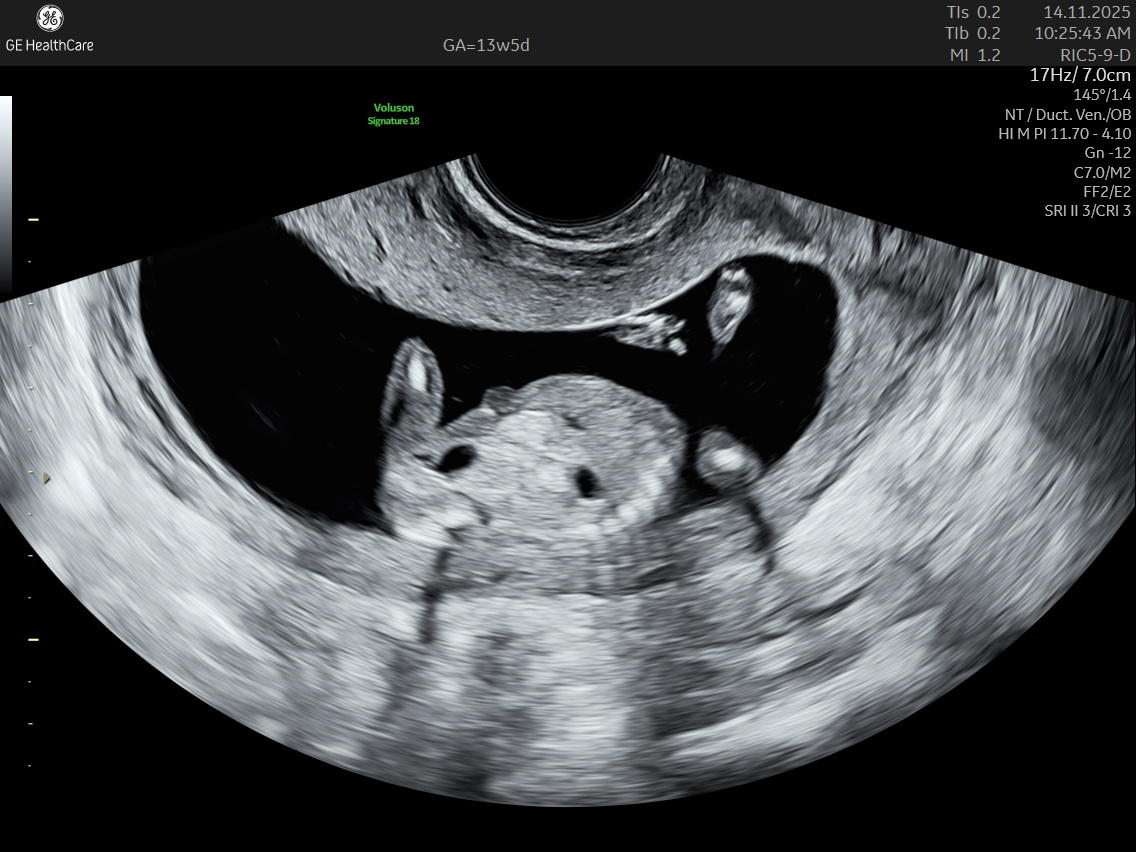

The NT scan is a non-invasive ultrasound examination conducted in the first trimester (12–13 weeks). It measures the nuchal translucency (the fluid at the back of the fetus’s neck) and combines it with the maternal blood test for a detailed risk profile. NT Scan is an important early screening test for Down syndrome (Trisomy 21), Edwards syndrome (Trisomy 18), and Patau syndrome (Trisomy 13).

- Absence or shortness of the nasal bone, which is a soft marker for genetic conditions like Down syndrome, although it does not mean there is a physical defect in the nose functionally.

Although the NT scan is mainly a screening tool and not diagnostic on its own, it can identify about 50% of major fetal abnormalities when combined with other assessments like blood tests and detailed ultrasound. The scan also helps to screen some basic anatomical structures during the first trimester, especially the fetal heart anatomy, brain, face, spine, stomach, abdominal wall, kidneys, bladder, and extremities to varying degrees depending on gestational age and maternal factors.